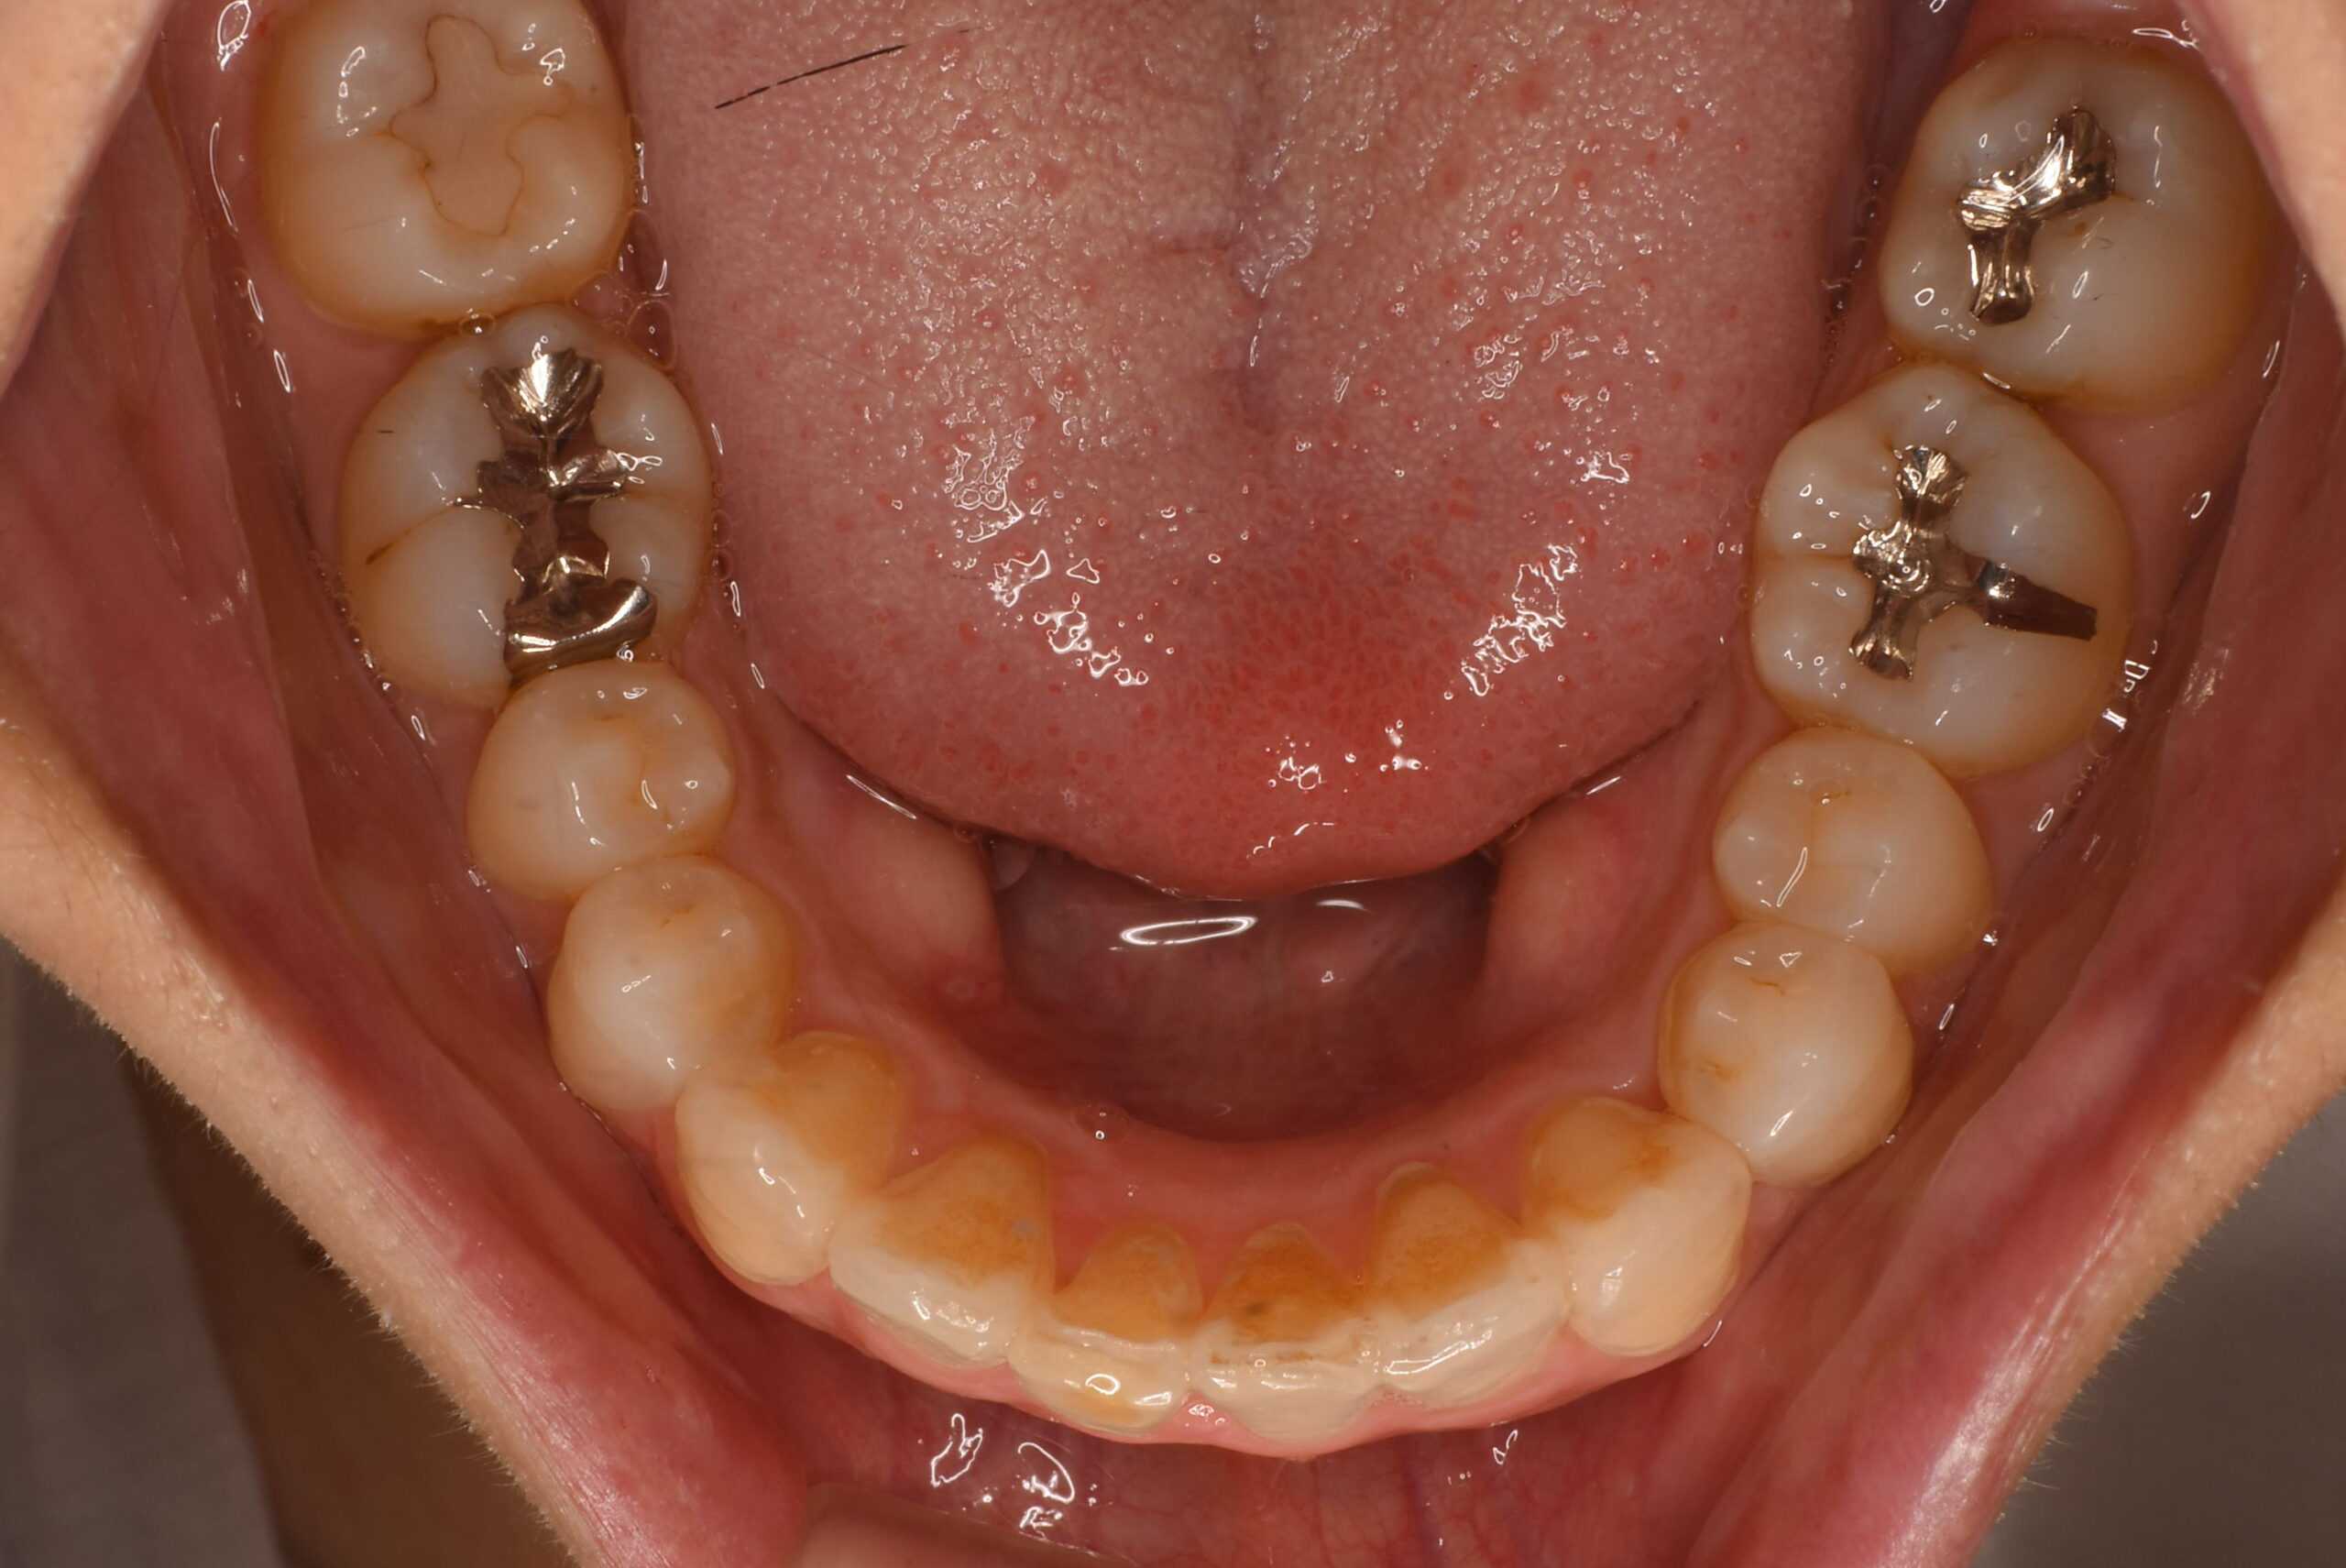

治療後_下顎咬合面

| 治療内容 | 患者様は、上顎前歯の突出や歯列の叢生(ガタつき)、笑った際に歯ぐきが見えすぎること(ガミースマイル)を主訴に来院されました。 診査の結果、抜歯を行うと歯軸の傾斜や歯列の陥没が懸念されたため、非抜歯でのインビザライン治療を計画しました。 |

- ・矯正治療中はプラークコントロール(PC)が不良になりやすく、う蝕(虫歯)や歯肉炎のリスクが高まります。 ・治療期間中はTBI(歯磨き指導)を適宜実施し、口腔衛生状態の改善を図りました。 ・アライナーの装着時間が不足すると、歯の移動精度や治療期間に影響を及ぼす可能性があります。 ・IPR処置部位では一時的に知覚過敏を生じることがあります。